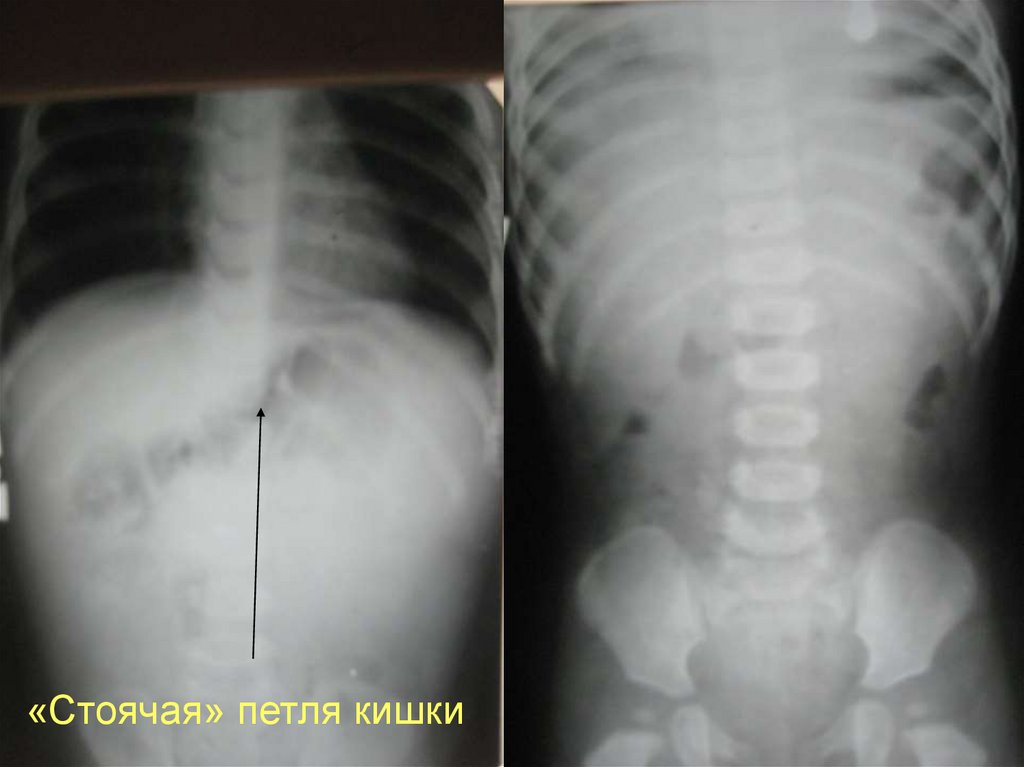

«Стоячая» петля кишки

63. Множе-ствен-ные газовые уровни

Множественные

газовые

уровни